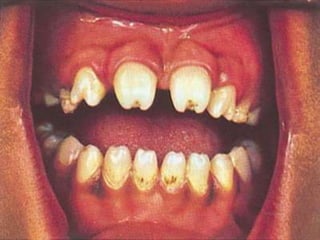

• Hutchinsons’ teeth

 Seen at 6yrs / later

 Permanent upper central incisors are shorter than the lateral

incisors

 Widely spaced

 Have a notch in the bitting edge

 Due to defective enamel formation

 Assume a peg / cork screw driver shape

 Other incisors may also be effected

• Mulberry / Moon’s molars:

First lower molars – commonly effected

Under developed & poorly enameled

Bitting surface - dome shaped with small projections of ill

developed cusps

More prone to caries

Usually lost in early life